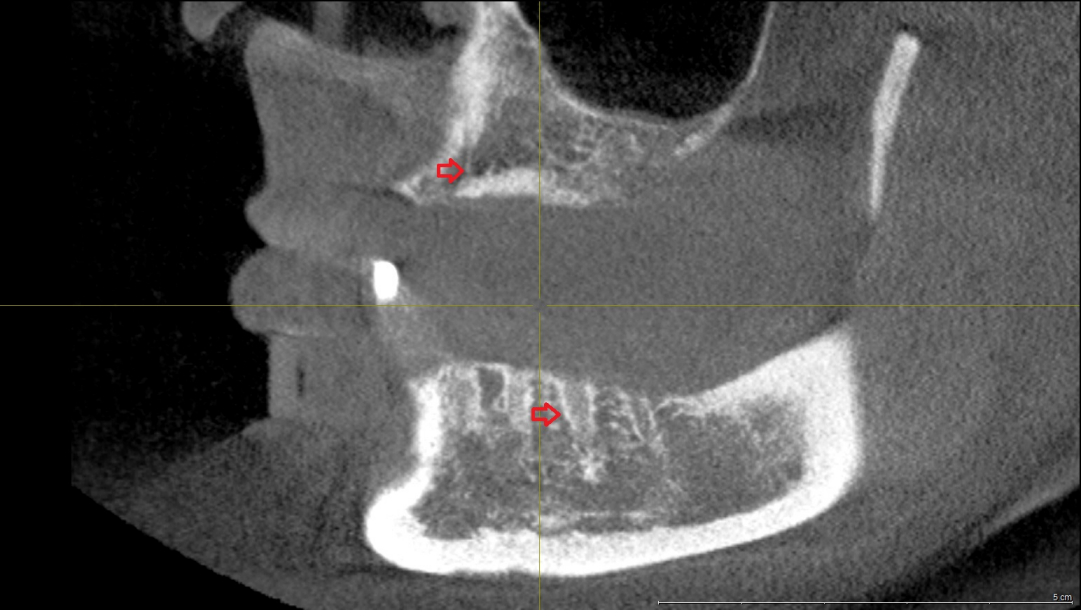

A panoramic radiograph obtained on the day of her visit on March 2017 revealed regions of osteosclerosis, subperiosteal bone deposition at the extraction sites, and persistent unremodeled bone in the alveolar sockets surrounded by periapical hypermineralized lines (Figure 2 [Fig. 2]). A generalized periodontitis combined with tooth loss and horizontal bone loss was also diagnosed radiologically. A digital volume tomography in sagittal view showed persistent bony trabecular architecture and absence of bony lysis – the classical radiologic signs of “persistent dry alveolar sockets” (Figure 3 [Fig. 3]).

Figure 3: Digital volume tomography (performed in March 2017). Sagittal view shows persistent bony trabecular architecture without bony lysis, indicating classical radiologic signs of persistent dry alveolar sockets. Arrows indicate the unremodeled alveolar sockets.